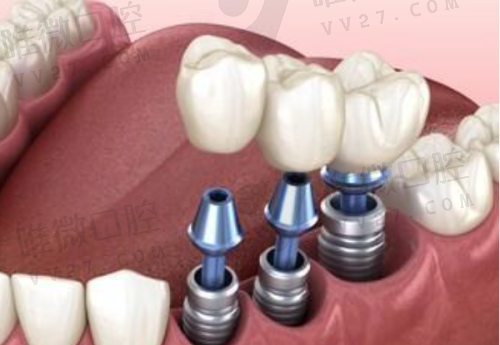

项目优势在于种植和正畸,医生技术稳定,而且价格合理:韩国登腾种植牙含冠仅从3680元起,相比市面动辄8000多的价格确实亲民不少。